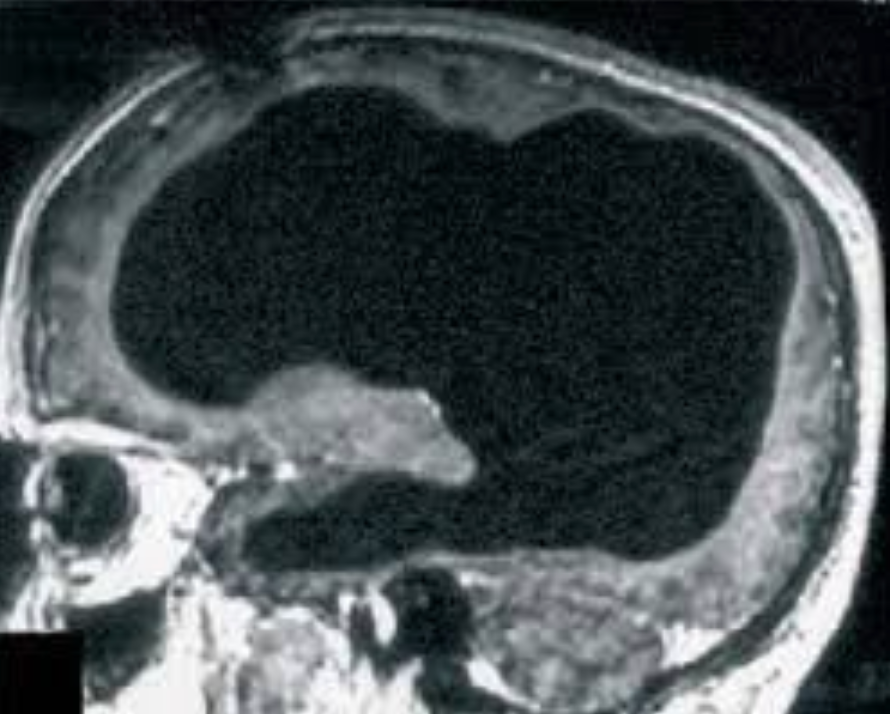

她刚刚度过了20岁生日,尽管在她原本应该充满沟回的大脑位置,只有一汪脑脊液和一小勺被称为“粉红色果冻”的残留组织。

亚历克斯出生时便被判了死刑,医生预言她活不过六个月,因为她的颅腔内几乎空无一物。不仅是额叶、顶叶这些负责高级认知的大脑半球全都缺失,连视觉和听觉中枢也荡然无存。

据她父亲描述,她颅内仅存的实体,是位于后部的一小块小脑和脑干,大小仅相当于成人的小指。这残留的微小组织,即那勺“粉红色果冻”,在传统医学视角下通常被视为仅能维持心跳呼吸的生物残渣。然而事实诡异得令人不安,亚历克斯不仅活着,她还能感知。

他的大脑皮层并未消失,而是被压成了一层薄纸贴在颅骨上(下图),如同被压扁的三明治,结构依然完整,神经连接依然存在。这证明的是大脑惊人的可塑性。

而亚历克斯的情况截然不同,她是真正的“缺失”,她的神经元不是被压缩,而是被液化吸收殆尽。因此,亚历克斯的生存比那位法国公务员更具颠覆性,她证明了人类可以在没有皮层“硬件”的情况下,依然维持某种形式的“软件”运行。